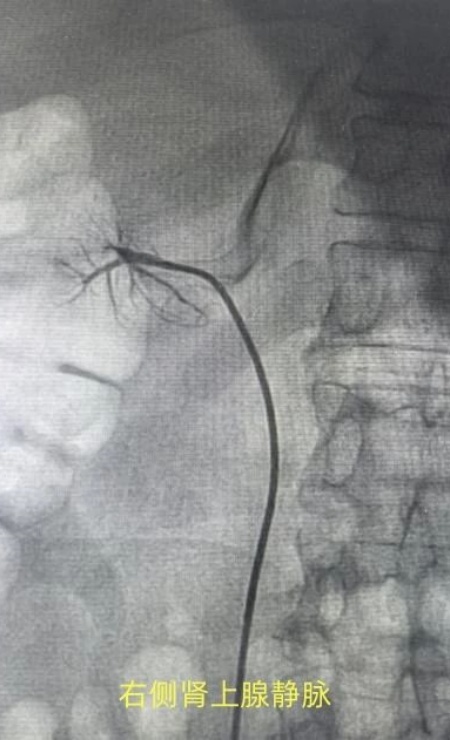

患者张xx,深受高血压困扰8年,血压却始终难以得到有效控制,本次入院前2天在家自测血压210/110mmHg,佟勤红主任带领团队对患者进行了全面、细致的评估后,高度怀疑患者为原发性醛固酮增多症。而双肾静脉采血,作为诊断该病手术治疗的“金标准”检查手段,能够通过精准检测双侧肾静脉血中醛固酮及肾素水平,明确肾上腺病变的侧别,从而为后续的个性化治疗方案制定提供关键依据。

手术当日,在佟勤红主任的精准指导下,心内一科手术团队凭借娴熟的操作技巧和丰富的临床经验,有条不紊地开展手术。从穿刺血管、置入导管到精准采集双侧肾静脉血,每一个步骤都严谨规范、环环相扣。整个手术过程顺利,患者生命体征平稳。目前,患者的血样已完成送检,确诊为单侧肾上腺腺瘤所致的原发性醛固酮增多症,患者可通过手术切除腺瘤,有望实现高血压的治愈。